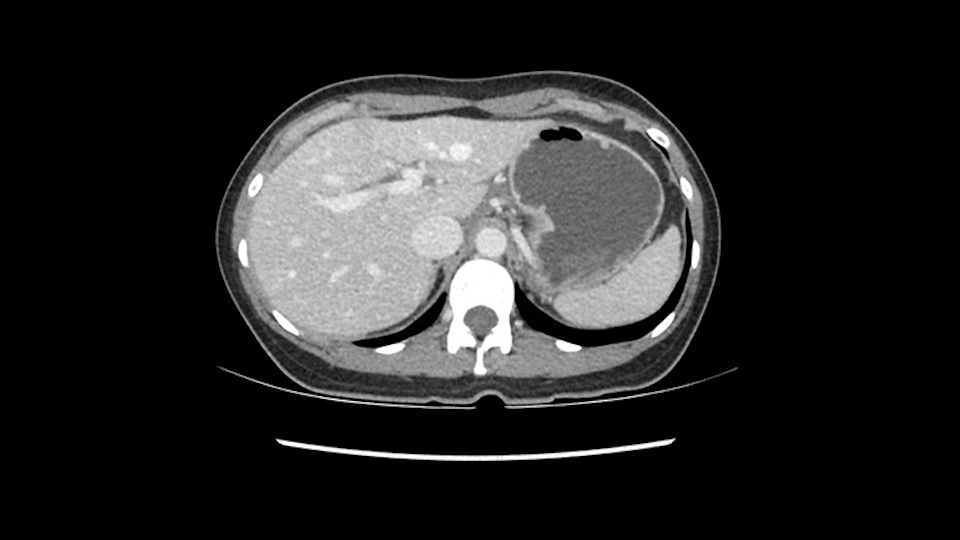

So if we look at the CT scan, on the axial, it’s a larger lesion. It’s about 6 or 7 or 8 centimeters. So it does look a bit threatening in terms of its resectability but if you really drill down deeply into the anatomy, and I think the coronal [imaging] is even better, you can see that the entire mass is on the patient’s left side of the falciform ligament. So it’s really only a left-sided tumor and not even really a left-sided tumor because Segment 4 is uninvolved anatomically.

None of the parenchyma is affected and this tumor is very exophytic; like many Hepatitis B hepatomas; and otherwise is resectable with either a wedge resection part of Segment 2-3 or a formal left lateral segmentectomy.

Some of my colleagues thought it may be involving Segment 4 and we’d need a formal left hepatic lobectomy, dividing anatomically: the left portal vein, left hepatic artery, left bile duct. But I didn’t think so, but you can see there is a challenge in terms of being certain where this tumor is located. So we’re prepared to do any of those 3 but my person view is that its going to be an exophytic tumor off of the left lateral segment and probably a wedge.

As I review the CT scan, we have both arterial and venous phases, the tumor is obvious. But I’ll start by saying that the liver itself does not appear to be cirrhotic to my eye. It’s got a normal contour and allied to that, that I do not see evidence of portal hypertension. The spleen is normal, there’s no collateral vessels. The tumor itself, I measured maximally at about 11 centimetres in diameter and I’m told the alpha fetoprotein is very high (over 10000), which is entirely consistent with this being a solitary hepatocellular carcinoma that is very exophytic. It seems to emanate off the inferior margin of Segment 3 (because that’s the falciform). I’ll start by saying that this is not transplantable. The tumor exceeds our guidelines for transplantation, but it's likely resectable based on normal liver and no portal hypertension.

So the issue with regards to resection. A left sided tumor. I believe I can see the falciform ligament right here so we’re looking at a resection of Segments 2, 3 of the left lobe of the liver. The left portal vein is right there. I think we’ll be wiser to take the left portal vein and therefore get well into Segment 4 and do a left hemihepatectomy. Certainly, one does not need to take the middle hepatic vein; it’s miles from the tumor.

The transection line will be a little more obvious. There’s a little patch of focal fat here in Segment 4b but we’ll describe the transection line probably through the mid portion of Segments 4a and b up to the top. Up at the top, the left hepatic vein can be taken. There’s a Segment 3 vein or the so-called falciform vein it’ll be rudimentary so I think we’ll be able to get around the left hepatic vein and leave the middle [hepatic] vein intact because it’s free of tumor.

What kind of procedure can we plan for this patient? It obviously has to be a left hemihepatectomy because most of the lesion is actually in Sg4. Can we do something which is less than a hemihepatectomy and just do only a segmental resection? The answer to that is that this vascular supply, if you are trying to ligate only the portal venous pedicle to the Segment 4, it is very close to the tumor and you will end up not having not a great margin as far as tumor resection is concerned so I would recommend a left hemihepatectomy and not just a partial or segmental resection. You can also see that it is crossing the falciform line and going on to Segment 2 and 3 so trying to do anything less than a left hemihepatectomy may not give the right kind of margins which we need for this tumor. Fortunately for us, the contours of the liver, which are very important to see in a Hepatitis B patient, there are no cirrhosis which I can see. The normal liver functions indicate that it's a well compensated Hepatitis B.

So in planning for this operation, as I look at the scans, I first visualize the arterial phase and I can see that there’s are a lot of big feeding arteries to this large tumor. Likely all the right side vessels feeding the right side of the liver: right hepatic artery and likely the Segment 4 artery are spared from the tumor. It’s likely the left hepatic artery is ramificating and giving feeding arteries to this tumor. It certainly looks like a large mass that its compressing other structures like the cava, the pancreas, the stomach; but I think there’s a plane and we can see that better in the venous phase. There’s a plane of separation between the gallbladder, the pancreas, the cava, that this tumor is abrupting but likely not invading. Usually, these masses actually don’t invade at that level and basically are pushing the tissues and once you open, you’re able to separate the tumor. Sometimes there’s some adhesions but you can actually separate and there’s usually no invasion.

The other thing I would do in this case is to certainly to assess the coronal phase as we can see in the coronal phase, this tumor looks like it's growing from Segment 3, and again I don’t think there’s involvement of the right side of the liver or even on Segment 4.

So in terms of planning on the surgery, I think there’s two clear options for this patient and that we’ll need to assess once we’re in the operating room. One option would be to do a Segment 3 resection. This tumor seems like it's hanging from Segment 3 so I think if we can get a good margin, that would be an option. Of course the other option is to do a left hepatectomy, preserving the middle hepatic vein, which is clearly not involved with the tumor.

The other option of course is to do an anatomical left hepatectomy. In that case, I will start mobilizing of course the left lobe and try to find the ligamentum venosum, take it down and go around the left hepatic vein. I think, importantly in these cases and in this case, as you can see in the venous phase, that’s clearly a moment to stop. Because the left hepatic vein is pretty close to the middle hepatic vein as sometimes it is so you may need to dissect a little bit the parenchyma on top of the left hepatic vein to be able to go around the left hepatic vein safely.